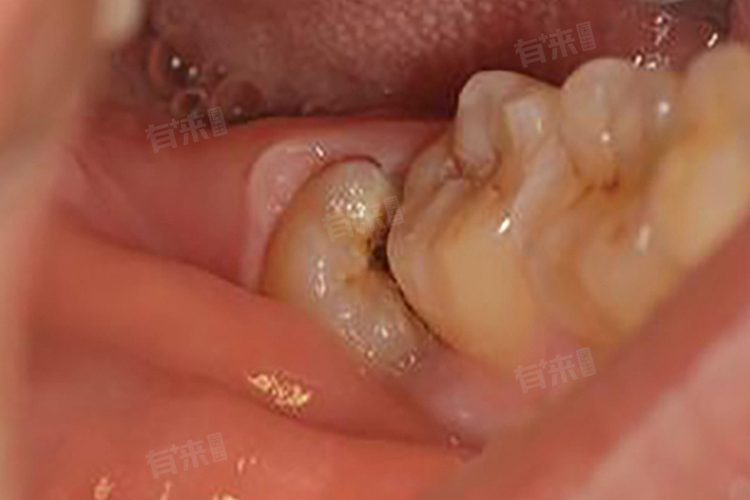

后槽牙拔除后是否需要立即进行种植牙修复,并不是一个一刀切的问题,而是需要结合缺牙位置、邻牙状况、咬合功能以及个人需求等多方面因素进行综合考量。

- 后槽牙位于口腔的深处,主要承担着咀嚼硬物的重要职责。如果这一位置的牙齿缺失而未得到及时修复,那么原本由该牙齿承担的咀嚼压力将不得不分摊给其他牙齿,这不仅会增加剩余牙齿的负担,还可能导致这些牙齿因过度使用而加速磨损。此外,由于后槽牙在口腔中的特殊位置,它的缺失可能不容易被察觉,但这并不意味着可以忽略其重要性。

- 当一颗牙齿被拔除后,周围的牙齿可能会逐渐向空隙处倾斜或移位,这种变化不仅会影响美观,更重要的是会改变原有的咬合关系,进一步影响到整个口腔的功能协调。特别是对于那些本身就有牙齿排列不齐或其他口腔问题的人来说,这种情况更加明显。一旦邻牙发生倾斜,不仅增加了后续治疗的复杂性和难度,也有可能导致更严重的口腔健康问题。

- 健康的咬合关系是保证良好生活质量的基础之一,后槽牙的缺失如果不加以修复,很容易导致对颌牙因为缺乏对抗而过长生长,即所谓的“超长牙”,这会直接干扰正常的上下牙齿接触模式,进而影响整体的咀嚼效率。长时间的不正常咬合还可能导致颞下颌关节紊乱病,表现为张口疼痛、关节弹响等症状,严重影响日常生活质量。